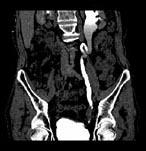

问题 男,76岁,无痛性肉眼血尿3个月,CT检查如图所示,下列说法错误的是 ( )

选项 A、考虑为左侧输尿管炎 B、考虑为左侧输尿管下段癌 C、左侧输尿管中上段扩张 D、左侧输尿管下段可见节段状不规则的软组织肿块影 E、左侧肾盂扩张积水

答案 A